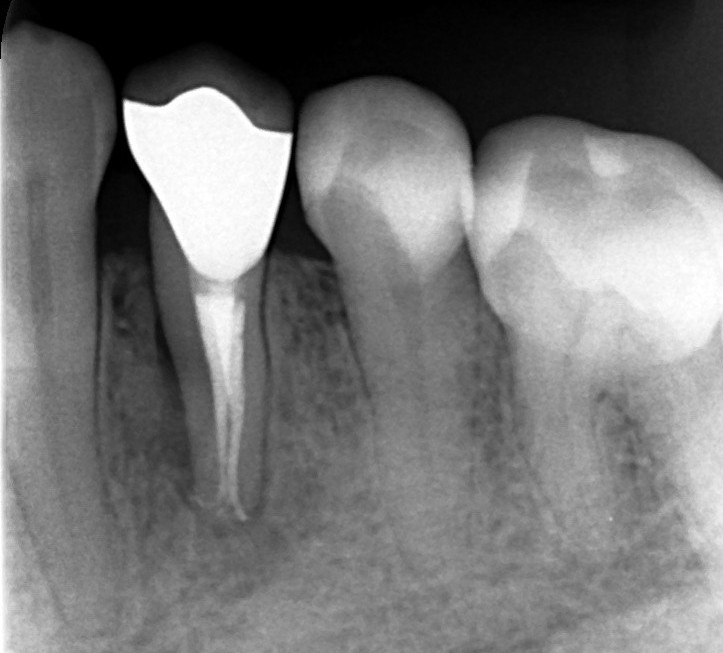

下顎小臼歯部

術前

術後